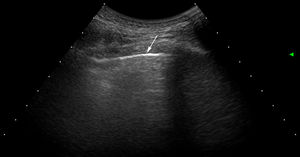

Interpretación del ultrasonidoEl hallazgo elemental a evaluar por US es la línea B, que se define como un artefacto de reverberación de base estrecha hiperecoica, que se extiende como un rayo láser hasta el borde de la pantalla. Estas líneas B por lo general no están presentes en pulmones de sujetos sanos16,17 (fig. 1). En cada espacio intercostal (EI) se registró el número de líneas B, posteriormente se registró y clasificó la suma total de todas las líneas B encontradas por el US pulmonar con base en la escala semicuantitativa propuesta anteriormente (0=normal, ≤5 líneas B; 1=leve, ≥6 y ≤15 líneas B; 2=moderada, ≤16 y ≥30 líneas B; 3=grave, ≥30 líneas B). Lo anterior con el objetivo de correlacionarse con los hallazgos de la TACAR.

ResultadosUn total de 77 pacientes con diagnóstico de ES fueron remitidos para ser incluidos en el estudio. Ningún paciente presentó, en la fase de reclutamiento, sospecha alguna de hipertensión pulmonar. Nueve pacientes fueron excluidos, ya que presentaron al menos un criterio de exclusión. El estudio finalmente se realizó en 68 pacientes con ES y 68 controles sanos. Un total de 952 EI en 68 pacientes con ES fueron examinados por US pulmonar. Las características demográficas y clínicas de la población de estudio se ilustran en la tabla 1. Veintiocho de los 68 pacientes (41,2%) mostraron signos de EPI por US en contraste con los controles sanos (4,8%) (p=0,0001). La figura 2 muestra diferentes cuadros de EPI detectados por US, incluyendo un cuadro de comparación entre US y TACAR.

Exámenes de US que muestran diferentes cuadros de EPI basados en el número de lineas B.

A. Solo hay una línea B (punta de flecha). B. Se distinguen 4 líneas B (puntas de flecha). Ambos casos presentan irregularidad pleural (flechas). C. Examen de US mostrando un espacio intercostal con 6 líneas B y neta irregularidad de la pleura en comparación con el cuadro TACAR de EPI (D).